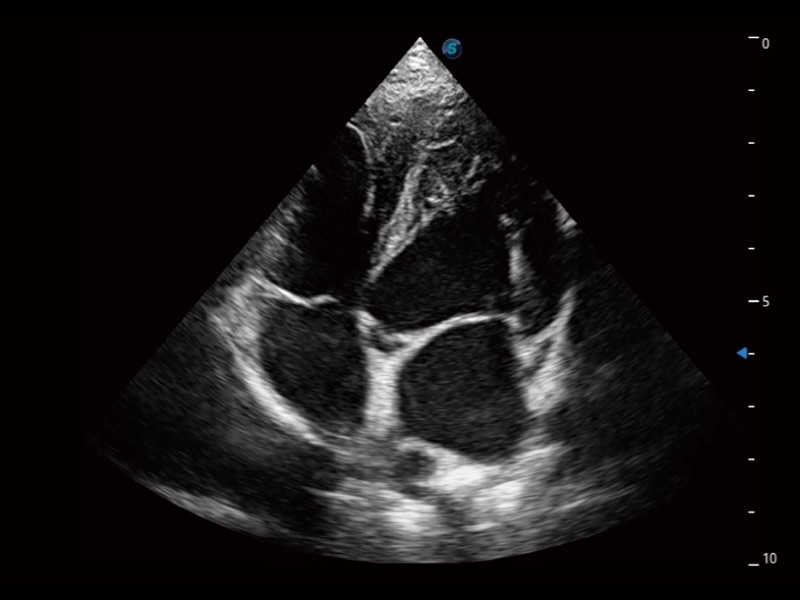

大型犬、马科、农场动物及大型异宠动物

通过360度任意调节3条M型取样线,在同一心动周期上观察心脏不同位置的运动曲线,得到准确的心功能测量数据,有效评估心肌运动及左心室功能。

ProPet 70专为动物医生设计,对不同的动物体型和生理结构作出了针对性的优化。通过动物影像专用软件,可满足个性化的应用需求,帮助动物医生获得更精确的诊断数据。